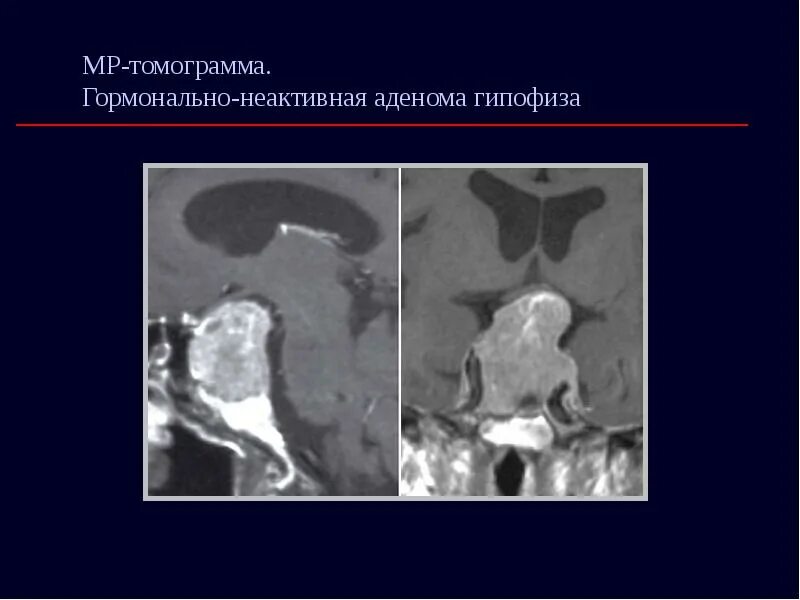

Воспаление гипофиза